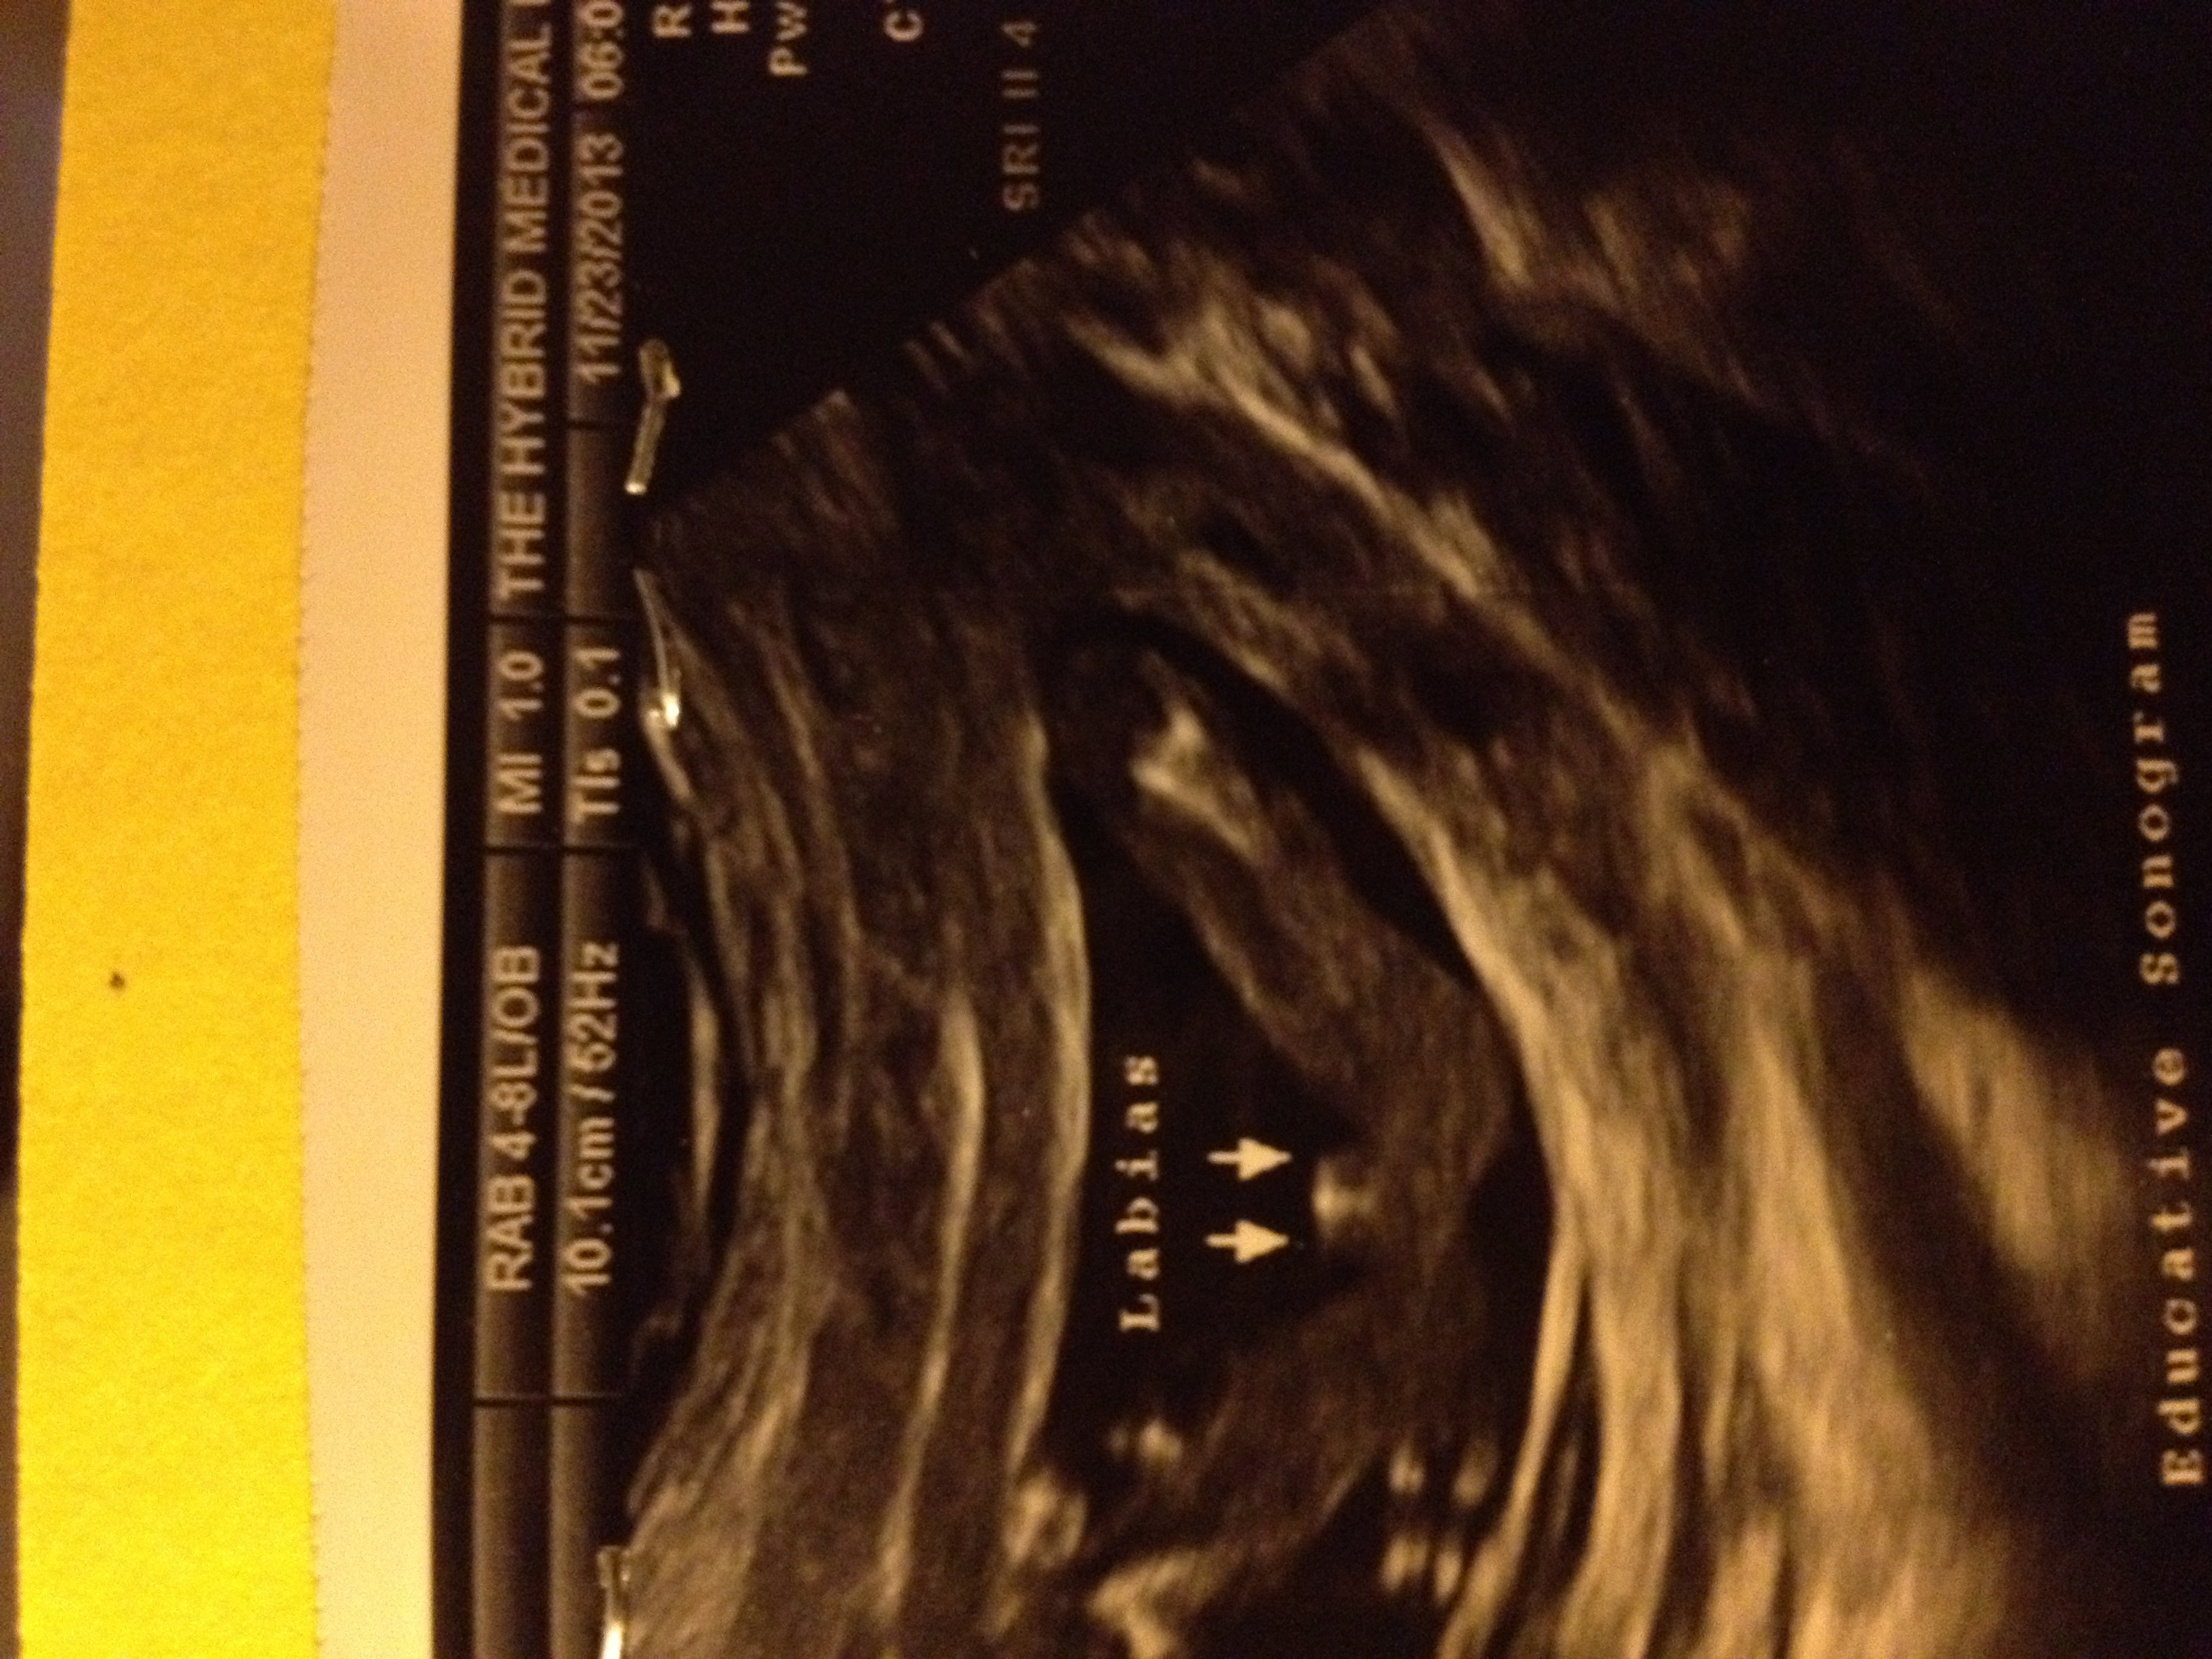

here ia my 16 week scan please let me know what you think Attachment 15418

Girl for sure! Congrats!